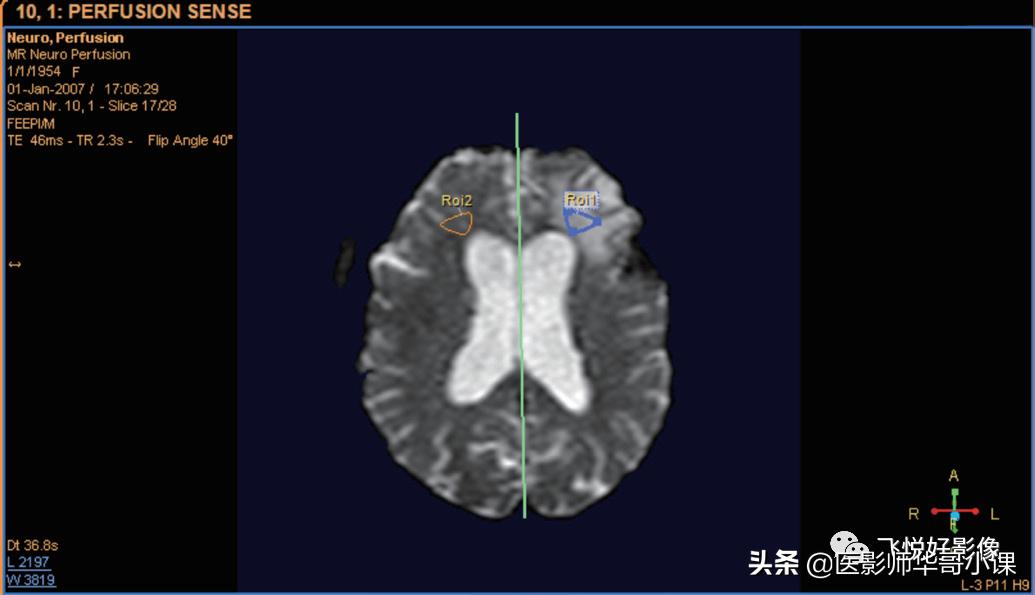

镜线使用

单击“显示镜射线”复选框,一个垂直镜线将显示在图像中间。拖动此线可将其移动或旋转。

图12.镜线

在绘制 ROI 时,可以启用 / 禁用镜线 ROI 的自动生成功能。单击“自动创建对侧 ROI”复选框。绘制 ROI,确定感兴趣区或者病变区域,完成后,将镜像绘制 ROI,自动创建对侧 ROI。

图13.镜像ROI

ROI数据会相应出现,图14左下方为表格形式,右上方为绘图形式,右下方为曲线形式。